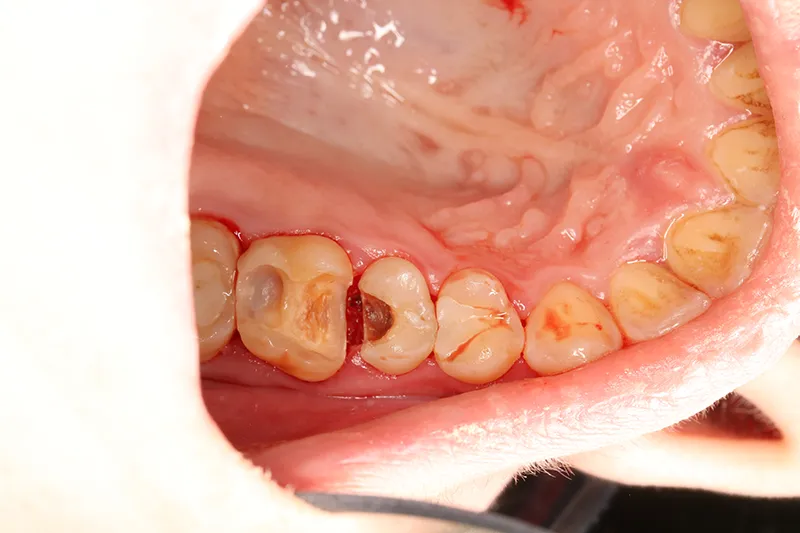

Необработанный кариес может вызывать образование свищей на деснах, что является признаком хронической инфекции